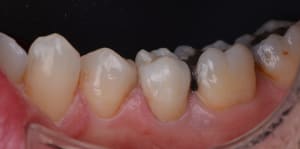

retouche_zircone_pqwgkr.png